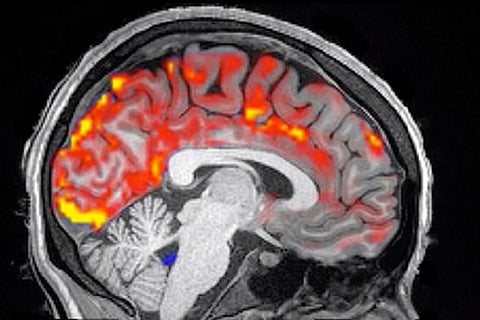

وقال الباحث المشارك في الدراسة البروفيسور لورا لويس: «إنَّ للنوم تأثيرًا كبيرًا على الدماغ أظهره تتبع حالة الدماغ أثناء النوم، وأوضحت الإشارات الكهربية المعروفة باسم (موجات دلتا) تدفق الدم بطريقة أكدت حماية الدماغ من أخطار السموم».

وأكَّد البحث الذي نُشِر في مجلة ساينس العلمية، أنَّ كتل البروتين الموجودة في المخ، تلعب دورًا في حدوث أسباب الخرف، حيث تشير الأبحاث السابقة إلى أنَّ تدفق السائل النخاعي ونشاط الموجات البطيئة يساعدان في التخلص من البروتينات السامة التي تضعف الذاكرة.